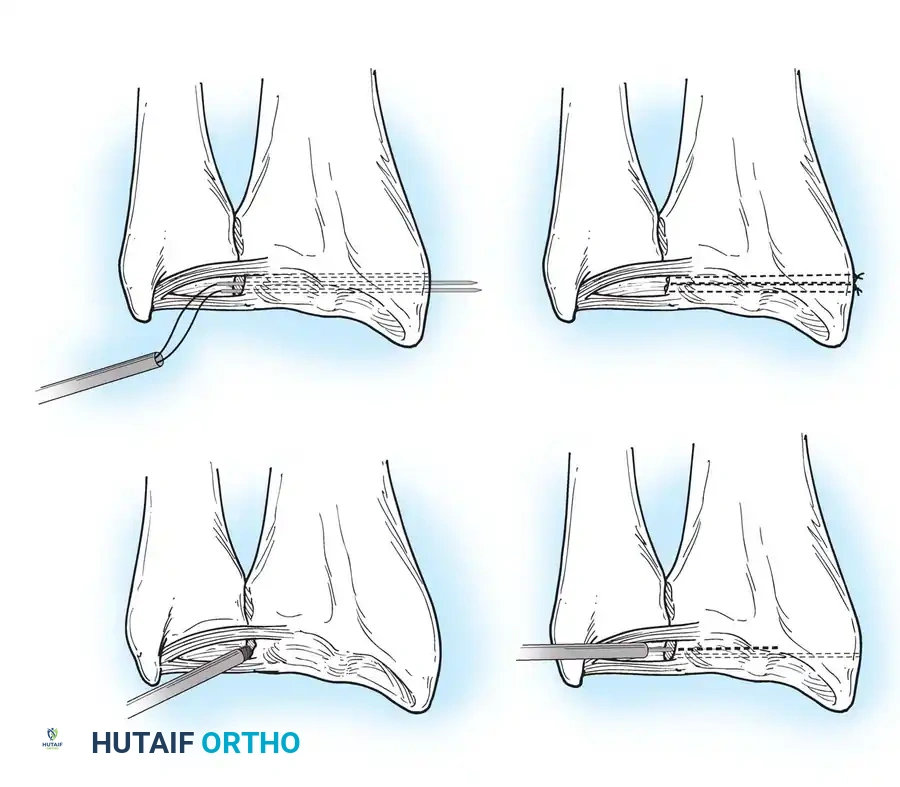

Preparation of the distal ulna: Drill holes are created at the fovea to facilitate transosseous suture passage for anatomic TFCC reattachment.

Transosseous Repair Technique:

1. Identify the foveal detachment arthroscopically or via an open dorsal ulnar approach.

2. Prepare the ulnar fovea down to bleeding bone using a burr or curette to stimulate a healing response.

3. Utilize a targeting guide to drill two converging osseous tunnels from the ulnar neck into the fovea.

Passing non-absorbable sutures through the osseous tunnels in the ulna to capture the peripheral edge of the TFCC.

- Pass strong, non-absorbable sutures (e.g., 2-0 FiberWire) through the TFCC using an outside-in or inside-out technique, then shuttle the suture limbs down the osseous tunnels.

The sutures are tied securely over the cortical bone bridge of the ulnar neck, restoring tension to the radioulnar ligaments.

- Tie the sutures over the ulnar cortical bridge with the forearm in neutral rotation to restore anatomic tension.